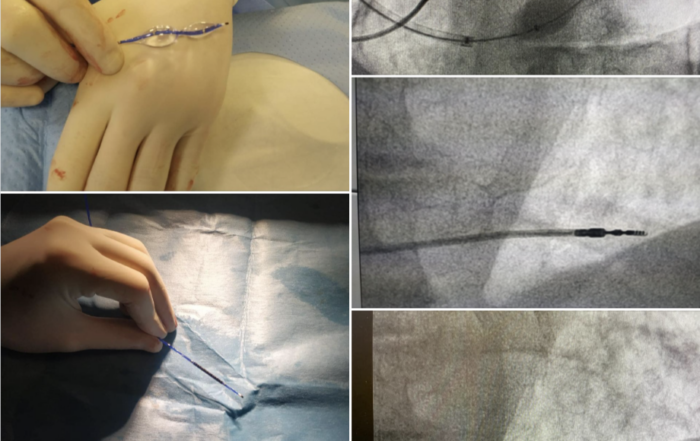

Pierwsza implantacja reduktora przepływu do zatoki wieńcowej w UCK WUM

W Pracowni Kardiologii Inwazyjnej Kliniki Kardiologii UCK WUM kierowanej przez prof. Marcina Grabowskiego wszczepiono reduktor przepływu do zatoki wieńcowej. Zabieg [...]